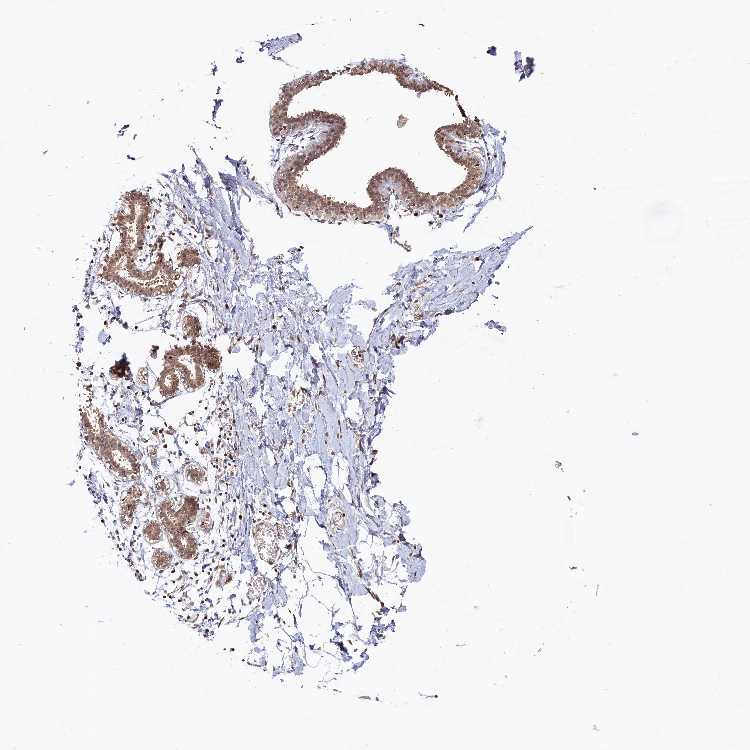

BREAST - Antibody stainingi

Antibody staining in the annotated cell types in the current human tissue is reported as not detected, low, medium, or high, based on conventional immunohistochemistry profiling in selected tissues. This score is based on the combination of the staining intensity and fraction of stained cells.

Each image is clickable and will lead to virtual microscopy that enables deeper exploration of all samples and also displays staining intensity scores, fraction scores and subcellular localization as well as patient and tissue information for each sample.

Antibody HPA039407Antibody HPA040057

Adipocytes Not detectedNot detected

Glandular cells MediumLow

Myoepithelial cells LowLow